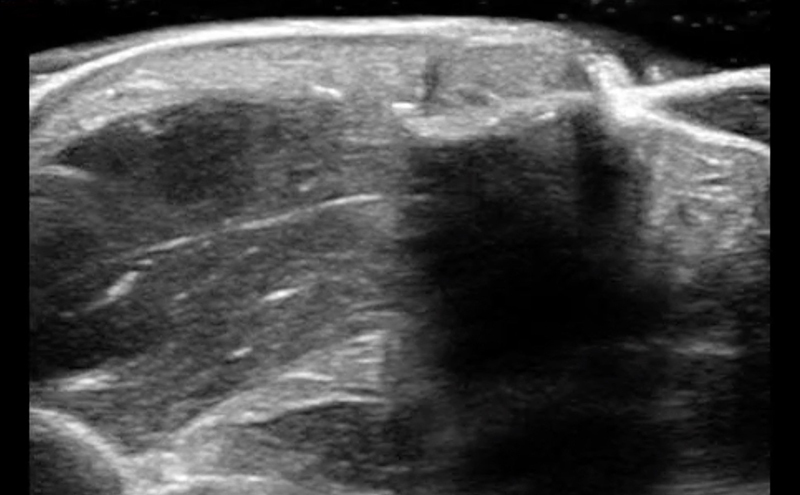

Anisotropy

Video 1. Anisotropy

Nerves can exhibit strong anisotropy

- Anisotropy refers to the changes in echogenicity of a structure as the angle of insonation is changed.

- Care must be taken to adjust the angle of insonation to ensure optimal nerve visualization.

- Tendons, ligaments and muscle also exhibit anisotropy.